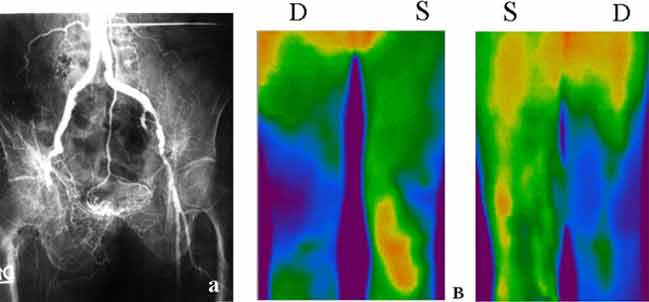

Рис. 1. Облитерирующий атеросклероз (а) Ангиография. Обтурация правой подвздошной артерии. (б) Выраженная гипотермия бедра и правой голени в обеих проекциях.